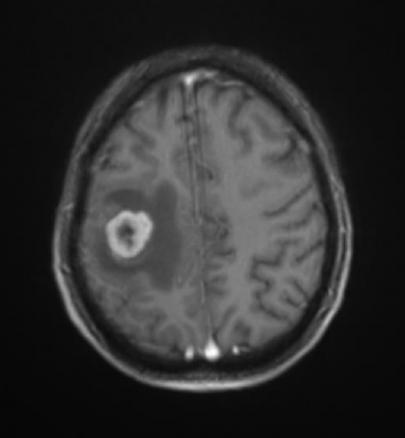

M. Roulleaux Dugage, La Revue du Praticien Lésion en cocarde frontale droite. Extrait de : Dossier progressif n°179